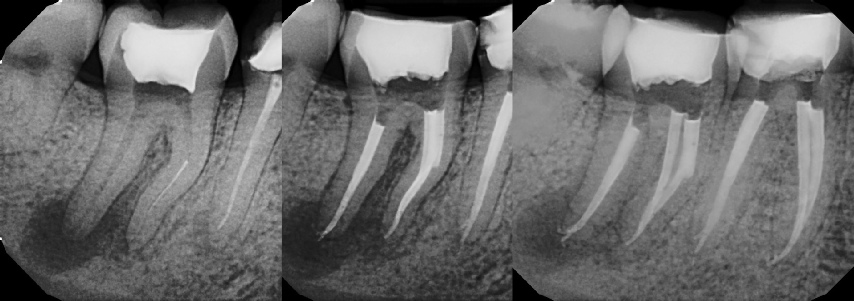

COMPLICATED ANATOMY LARGE LESIONS CALCIFIED CANALS PERFORATION / RESORPTION SEPARATED INSTRUMENTS SURGICAL CASES RETREATMENT / pOST REMOVAL OPEN APICES ACCESS THRU CROWNS Root Canal Case Portfolio

Pre-op Post-op 1 Post-op 2